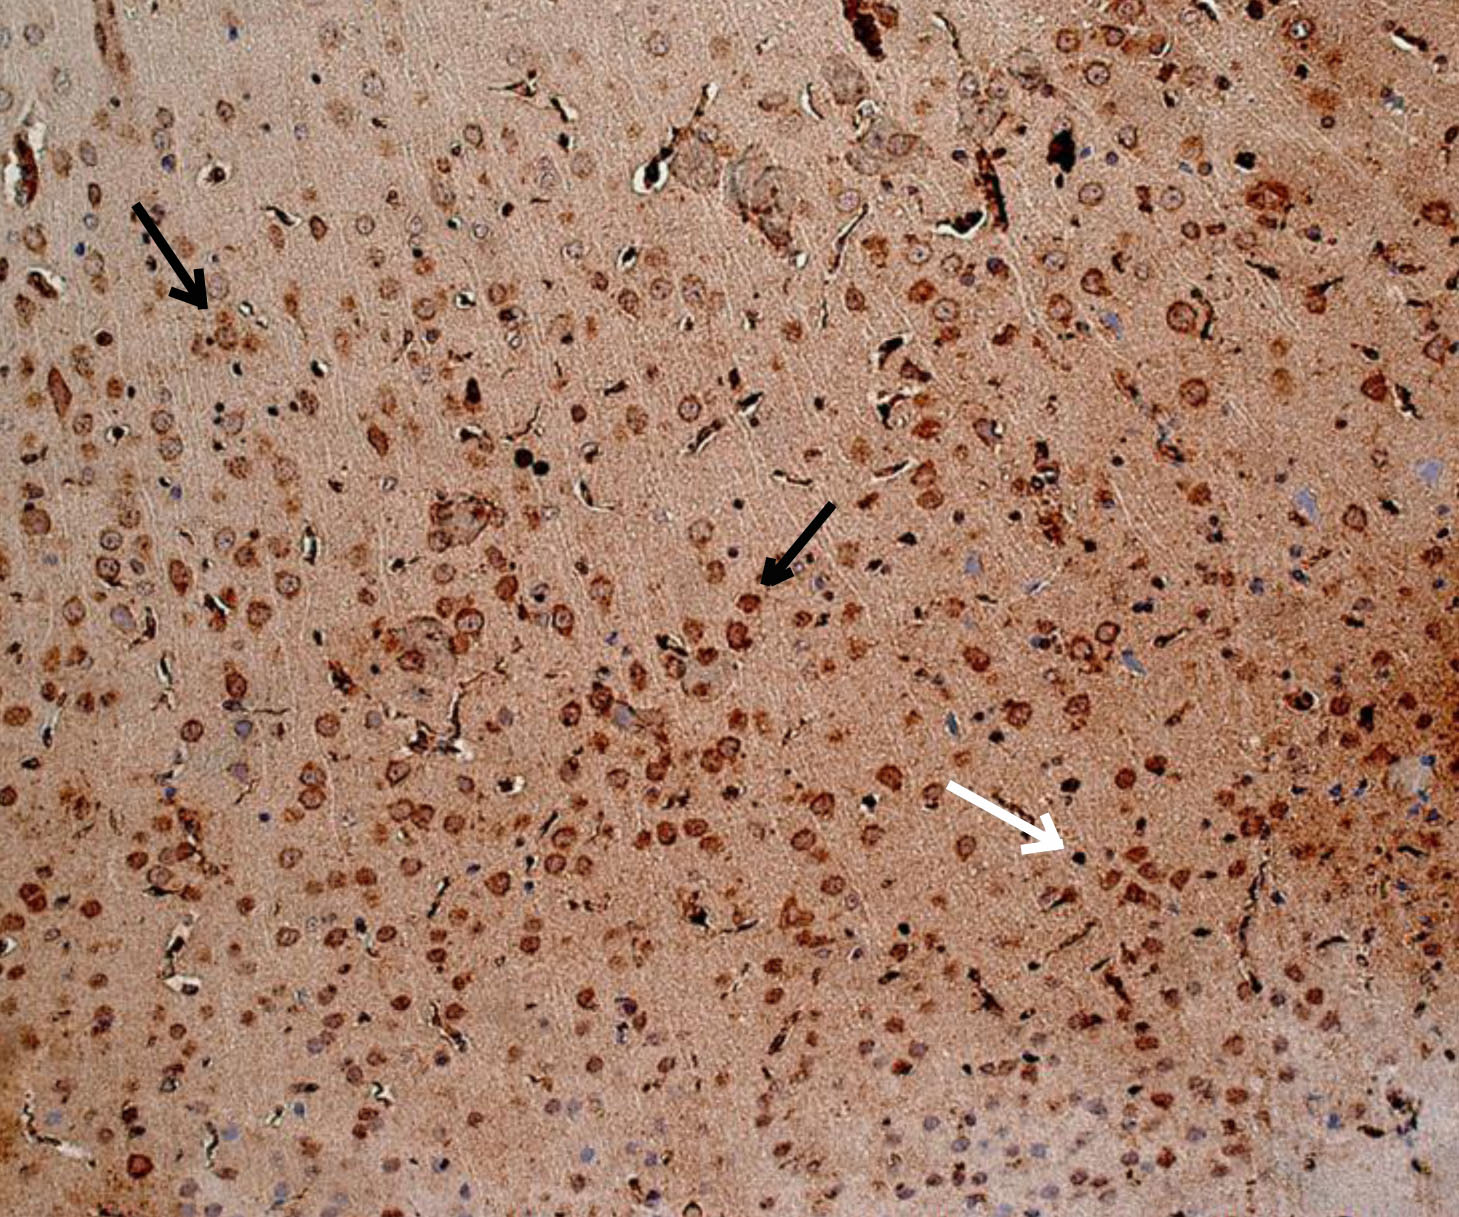

Рис. 1. Интактное животное – цитоплазматическая экспрессия ИРМ от слабой до умеренной степени. Иммуногистохимическое исследование, антитела против IL-6. Увеличение ×200. Черные стрелки – экспрессия в неповрежденных нейронах. Белые стрелки – экспрессия в нейропиле

При оценке результатов ИГХ исследования коры 19-месячных крыс без СД (интактных) была выявлена слабая равномерная экспрессия ИРМ IL-6 во всех слоях первичной и вторичной соматосенсорных областях коры головного мозга. В моторной, а также ретроспленальной коре была обнаружена цитоплазматическая экспрессия IL-6 в перикарионах нейронов от слабой до умеренной степени. У отдельных животных отмечалось наличие умеренной экспрессии IL-6 в базальных отделах коры. Преимущественно экспрессия ИРМ IL-6 определялась в цитоплазме неповрежденных нейронов, реже в нейропиле. В группе животных с экспериментальным СД1 без лечения наблюдалось увеличение выраженности экспрессии ИРМ IL-6 от умеренной до выраженной степени в сравнении с группой 19-месячных животных без СД. Характер экспрессии схож с характером экспрессии у 19-месячных животных без СД. Цитоплазматическая экспрессия ИРМ IL-6 также наблюдалась в моторной и ретроспленальной коре, локализация ИРМ IL-6 определялась в перикарионах нейронах пирамидного, внутреннего зернистого, ганглиозного слоев и в микроглии. В группах фармакокоррекции сукцикардом и аминалоном в сравнении с группой животных с СД1 без лечения наблюдалось снижение выраженности экспрессии во всех областях коры головного мозга, а в базальных отделах вплоть до исчезновения ИРМ IL-6 (рис. 1–4).